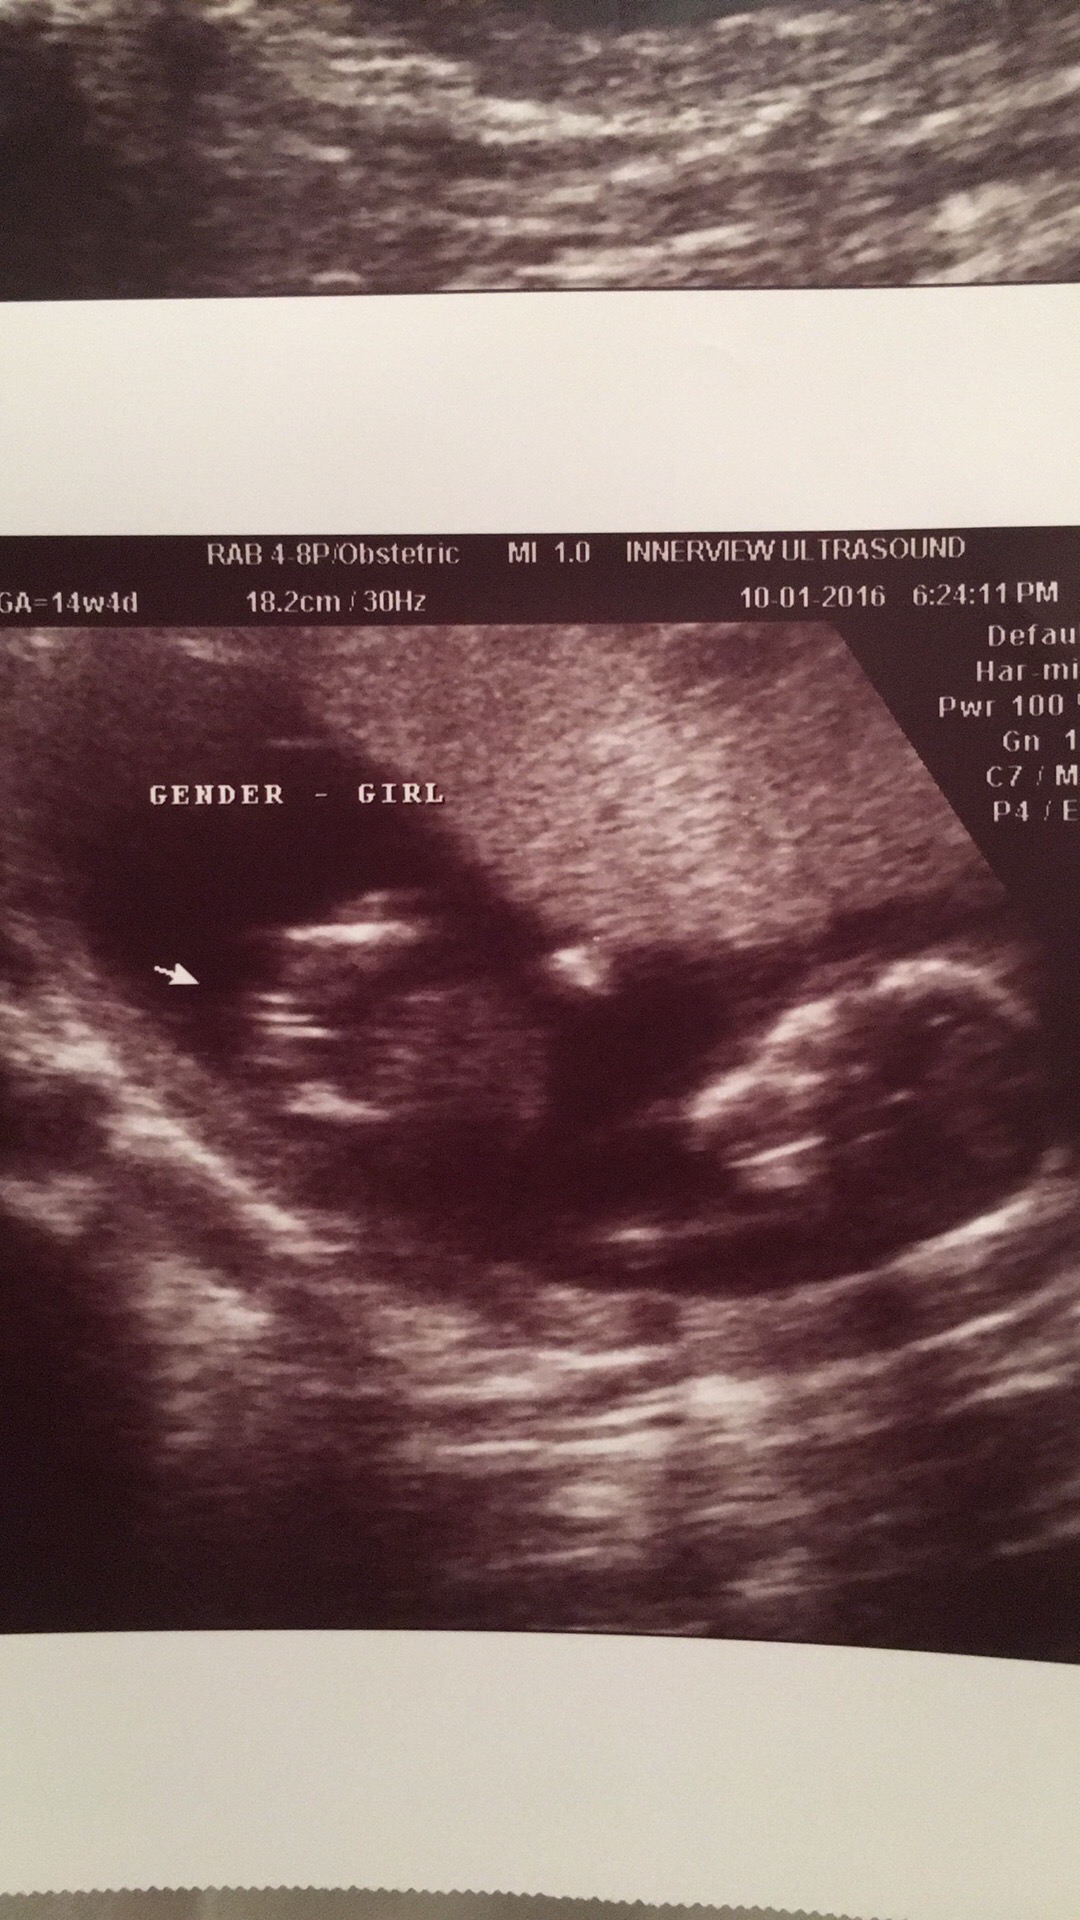

Hi ! I'm currently 17weeks pregnant. I had an early gender scan at 14wks4d. We have 3 boys so when we were told girl we were amazed and so happy !! Can I please take a look and confirm ???? Attachment 33423

Second picture looks very girly too me.

Yes, looks girly

GIRL

looks girly. Congrats!